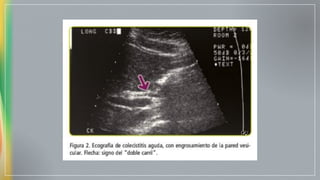

Diagnóstico - Pruebas de imagen

Ecografia Alta sensibilidad y

especificidad

Detecta cálculos calcificados (15% colesterol, 50%

pigmentados)